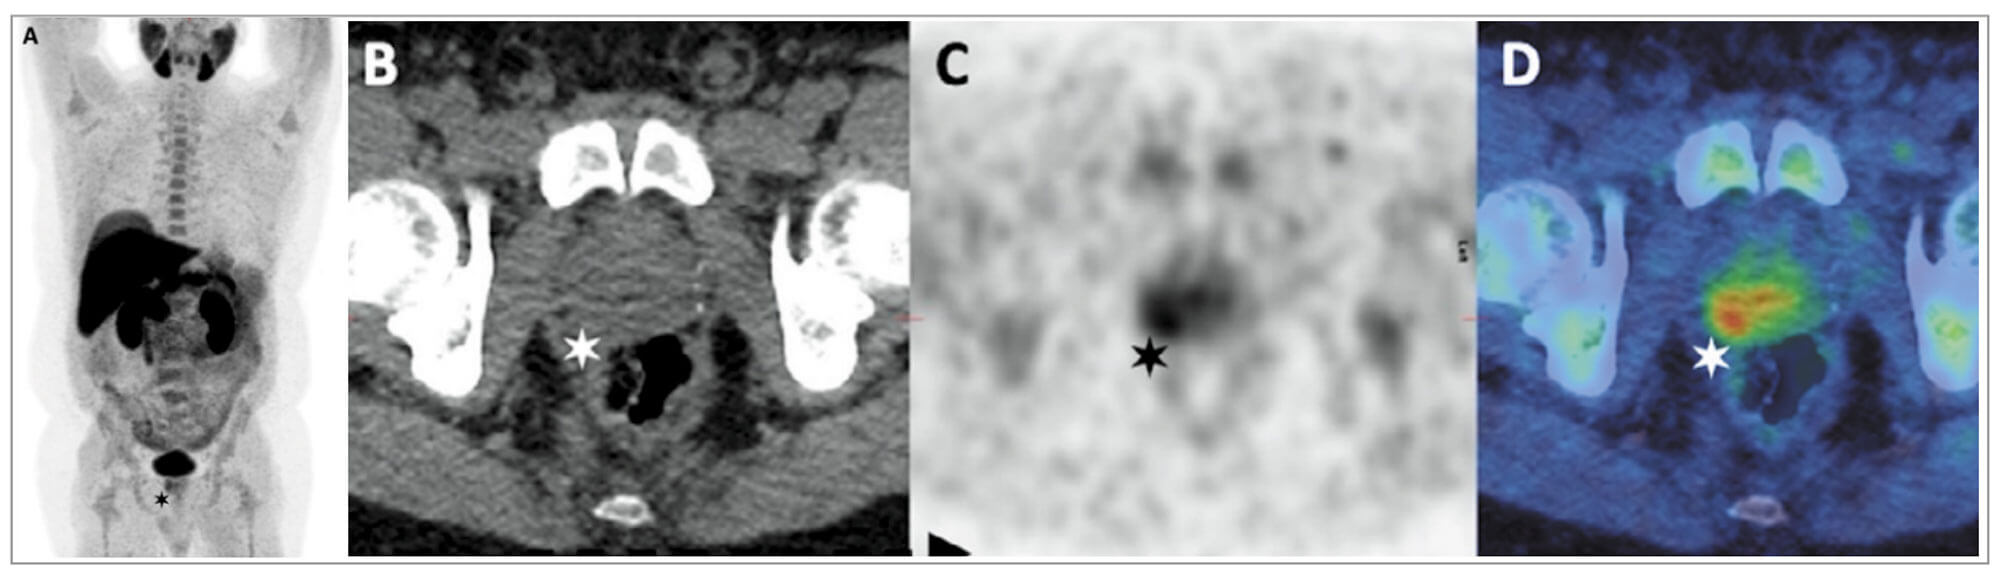

Figure 1: Choline PET-CT in staging of CaP. PSA 9.3ng/mL, T2aN0 on mpMRI, GS 4 + 3.

A & C: PET B: Axall CT D: Fused PET-CT images

Images demonstrate a choline-avid right basal prostatic tumour.

Choline PET-CT is superior to conventional imaging for extra-prostatic disease but has limited accuracy in differentiating between benign and malignant intra-prostatic pathologies (Figure 1). Prospective studies in patients with intermediate and high-risk CaP, have reported reasonable sensitivities (45-73.2%) but high specificities (87.6-96%) for nodal disease [5]. A meta-analysis of 10 choline PET-CT studies, in a total of 441 patients, confirmed a pooled sensitivity of 49% but a high specificity of 95% for nodal disease [6].